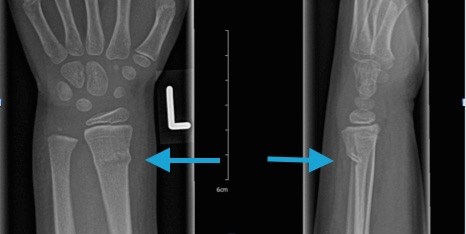

골막이 두껍고 뼈가 유연하기 때문에 뼈가 한쪽 만 부러지는 경우가 생기는데 패이는 형태의 green stick fracture 나 한쪽 피질 골이 접히는 것처럼 보이는 Torus fracture 등의 형태로 성인에서 볼 수 없는 골절 양상이 생길 수 있습니다. 또한, 가소성이 매우 높기 때문에 Wolf's law 등을 고려해 보았을 때 어느정도 근육과 해부학적인 힘의 매커니즘 형태로 (주로 이전의 모습) 복구하려는 모습을 보일 수 있습니다. 골절의 변형 규모가 매우 커도 단순한 석고고정 치료만으로도 치료가 가능한 이유입니다. 물론, 이러한 치료 판단 기준은 반드시 정형외과 전문의를 통해 이루어져야 합니다.